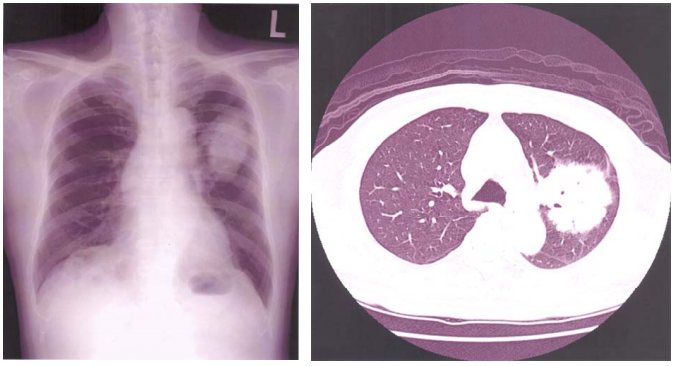

73 72 歲男性,因咳嗽、胸悶及倦怠持續半年,胸部 X 光及 CT 如圖,則最正確的診斷應為:

(A)肺癌(Lung cancer) (B)慢性左肺動脈栓塞(Chronic Lt. pulmonary artery embolism) (C)左肺上葉膨脹不全(Lt. upper lobe atelectasis) (D)縱膈腔腫瘤(Mediastinal tumor)